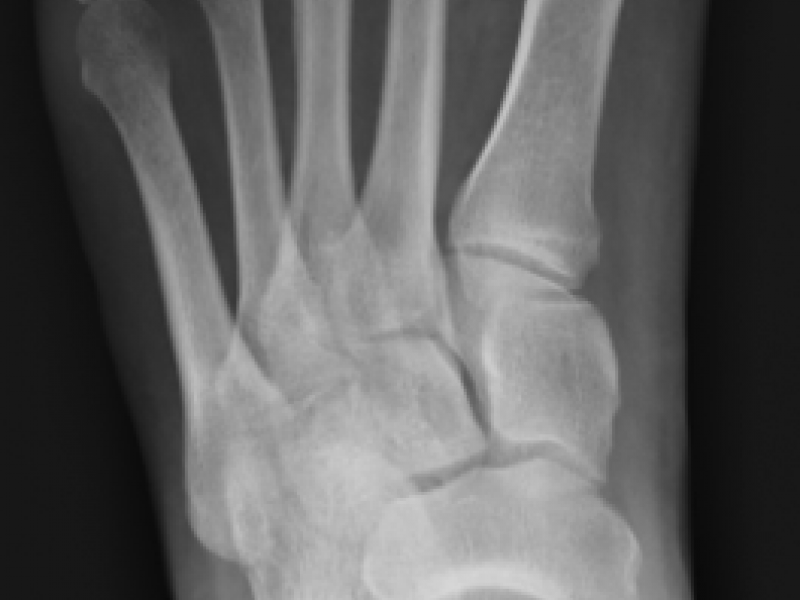

Back to Basics: First Metacarpal Fractures

Three types: Extra-articular, Intra-articular, Sesamoid Bone

What's the Diagnosis? By Dr. Erica Schramm

A 22 yo F with no past medical history presents to the ED